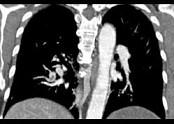

问题 男,56岁,食管癌术后,胸痛,呼吸困难,结合CT图像,最可能的诊断是 ( )

选项 A.食管癌肺转移 B.肺栓塞 C.支气管扩张 D.肺水肿 E.肺不张

答案 B